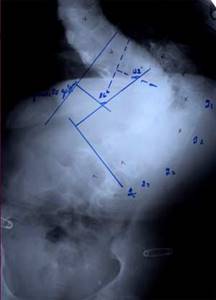

| Больной З-ч. 13 лет Сколиотическая деформация II степени грудного отдела позвоночника. Рентгенограмма позвоночника до операции |

Результат оперативного лечения. Коррекция 100% |